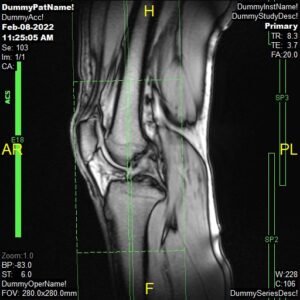

T2 Sagittal ISO

Parameters

Sample Image